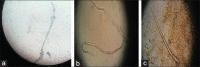

Strongyloides stercoralis (SS) is one of the most overlooked helminthic infections despite being highly endemic in tropical and subtropical areas. In immunocompromised patients, especially those on long-term steroids, infection can often escalate to fatal dissemination into major organs. We present a compendium of two immunocompromised patients, who were on high-dose steroids and presented with worsening neurological status. Cerebrospinal fluid analysis was notable for larvae of SS as diagnosed by direct visualization. A syndrome of SS hyperinfection with dissemination was made after stool, and sputum samples also revealed SS larvae. SS is an elusive disease and should be considered early on, especially in endemic regions like India. Early diagnosis and prompt initiation of antihelminthic therapy is indispensable for favorable outcomes.

Figures